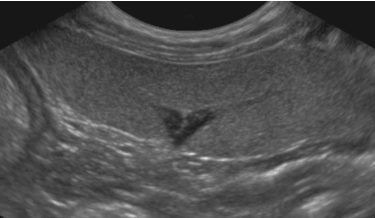

15 - De quel organe s'agit-il ?

A - Du Noeud lymphatique hépatique

B - De l'Ovaire Gauche

C - De la Surrénale Gauche

D - Du Noeud Lymphatique hypogastrique

16 - Où pouvez vous trouver cette même image échographique ?

A - En suivant la veine rénale Gauche

B - Entre le Rein Gauche et l'Aorte

C - Entre le Foie et l'Estomac

D - Entre le Rein Droit et la ligne médiane

E - En suivant la veine cave caudale

17 - De quel organe s'agit-il ?

A - De la Vessie

B - Du colon ascendant

D - Du Jéjunum

18 - Sur cette même image échographique, que pouvez dire ?

A - Présence de calculs

B - Présence de signe d'inflammation

C - Présence d'une lipidurie

D - Présence d'une masse polypoïde intrapariétale

Question 15 : Réponse C

Question 16 : Réponses A,B

Question 17 : Réponse A

Question 18 : Réponse C